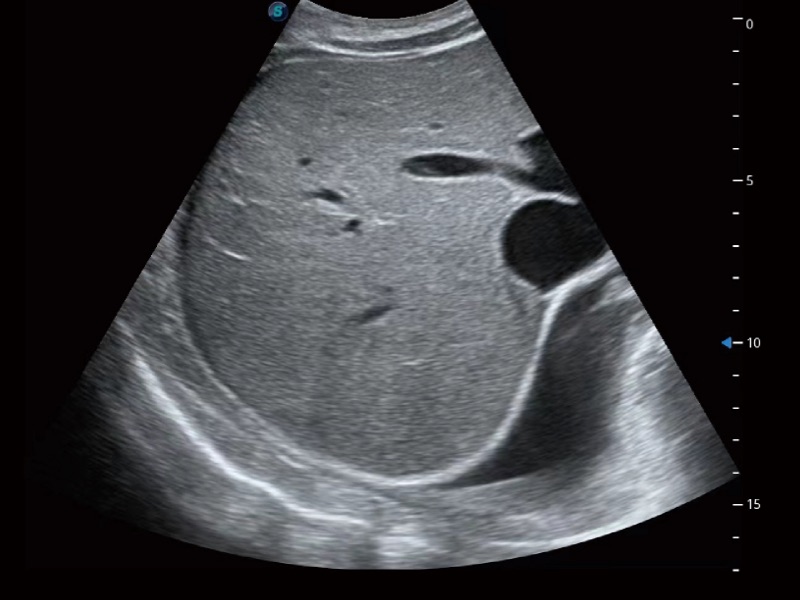

腹部應(yīng)用

超聲檢查得益于實(shí)時(shí)性、經(jīng)濟(jì)性、便捷性,目前廣泛的應(yīng)用于臨床工作中,超聲檢查設(shè)備已成為幫助臨床醫(yī)生輕松地完成診斷工作的好伙伴。P20 Plus集成了一整套包含了腹部、心血管、小器官、婦產(chǎn)科等全面臨床應(yīng)用功能,輕松應(yīng)對各種臨床問題。